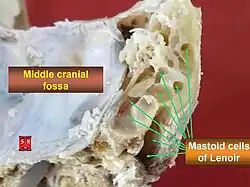

Mastoiditis is the result of an infection that extends to the air cells of the skull behind the ear. Specifically, it is an inflammation of the mucosal lining of the mastoid antrum and mastoid air cell system inside[1] the mastoid process. The mastoid process is the portion of the temporal bone of the skull that is behind the ear. The mastoid process contains open, air-containing spaces.[2][3] Mastoiditis is usually caused by untreated acute otitis media (middle ear infection) and used to be a leading cause of child mortality. With the development of antibiotics, however, mastoiditis has become quite rare in developed countries where surgical treatment is now much less frequent and more conservative, unlike former times.[2]

The pathophysiology of mastoiditis is straightforward: bacteria spread from the middle ear to the mastoid air cells, where the inflammation causes damage to the bony structures. Streptococcus pneumoniae, Streptococcus pyogenes, Staphylococcus aureus, Haemophilus influenzae, and Moraxella catarrhalis are the most common organisms recovered in acute mastoiditis. Organisms that are rarely found are Pseudomonas aeruginosa and other Gram-negative aerobic bacilli, and anaerobic bacteria.[7] P. aeruginosa, Enterobacteriaceae, S. aureus and anaerobic bacteria (Prevotella, Bacteroides, Fusobacterium, and Peptostreptococcus spp.) are the most common isolates in chronic mastoiditis.[8] Rarely, Mycobacterium species can also cause the infection. Some mastoiditis is caused by cholesteatoma, which is a sac of keratinizing squamous epithelium in the middle ear that usually results from repeated middle-ear infections. If left untreated, the cholesteatoma can erode into the mastoid process, producing mastoiditis, as well as other complications.[4]